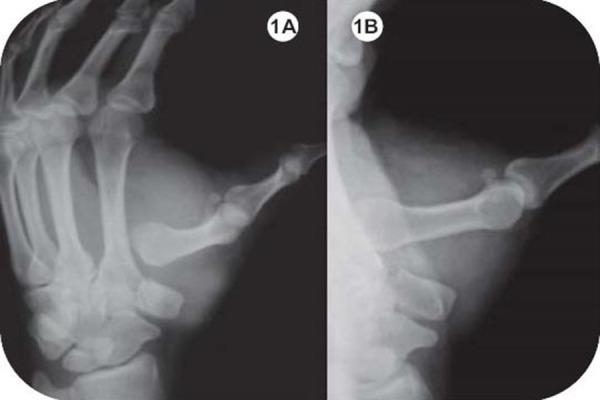

Isolated dislocations of the trapezio metacarpal joint without associated fracture has been reported very rarely in the literature. There are reports of associated injuries like fracture of the trapezium, dislocation of the metacarpophalangeal joint and fractures of the base of the thumb metacarpal.

Authors report a case of isolated carpometacarpal dislocation of the right thumb, in an adult, successfully managed conservatively. At 15 months follow up the patient had full function of the hand without any clinical or radiological evidence of instability or posttraumatic arthritis.